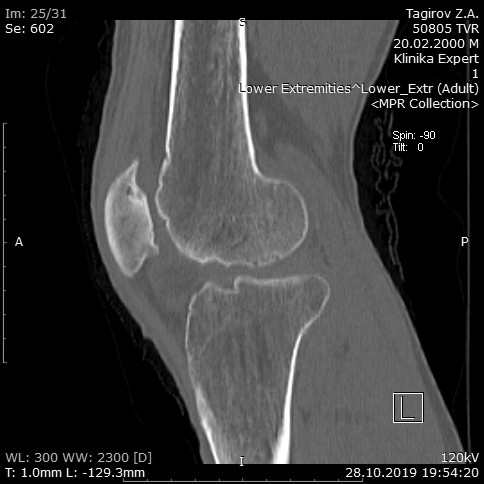

Мужчина, 19 лет. Боли в коленном суставе около 4 лет, латеральная часть колена. Травмы не было, заболевание развивается постепенно. Эпизода похожего острый гонит не было. Ранее проживал в другом субъекте РФ, где в 2018г при РГ графии выявлен несросшийся перелом правого надколенника, оперирован, костный шов лавсаном. Боли сохраняются. Сейчас обратился в нашем городе к травматологу, пришел к врачу сразу с результатом КТ. Картина врачом трактована как несросшийся перелом правого надколенника + грубые проявления ДОА КС справа. Сейчас госпитализирован, готовится к оперативному лечению (попытка пластики и фиксации "перелома" надколенника, либо удаление фрагмента, "отломка"). Ходит без трости, движения в суставе довольно активные, крепитация грубая. разгибание до 170-175*, сгибание 90* и более. Контуры сустава деформированные. Синовита нет. Мягкие ткани без воспаления. Связки стабильные. Анализы крови и мочи нормальные. Мое мнение - это пателла бипартита справа (хотя чаще - двусторонняя) + грубый ДОА. Исключать туберкулез и т.п. Оперировать надколенник не нужно. Больше снимков https://yadi.sk/d/EVavMn3W1B9zww

Конечно это - пателла бипартита.

Ткани совершенно спокойные, фрагменты надколенника связаны фиброзной тканью интимно, крайне плотно, подвижность на глаз не видна. Конечно, никакого результата фиксация лавсаном не имела по всей разделяющей линии. Малый фрагмент выделен по линии, фиброзная прослойка удалена, если на основной части пателлы удалось обнажить губчатую кость для контакта, то малый фрагмент, напоминает керамику, остеосклероз на весь объем. Фиксация и компрессия по Вебер. Удалось немного заглянуть в сустав - синовит минимальный, без примесей. Латеральный мыщелок бедра выглядит как в кислоте побывал.

Мнение коллег - дисконгруэнтный в силу особенностей развития надколенник деформировал мыщелки. Надколенник фиксирован, в перспективе - эндопротез КС.

Для меня причина грубейшего латерального ДОА по прежнему непонятна. Бипартита тут не при чем.